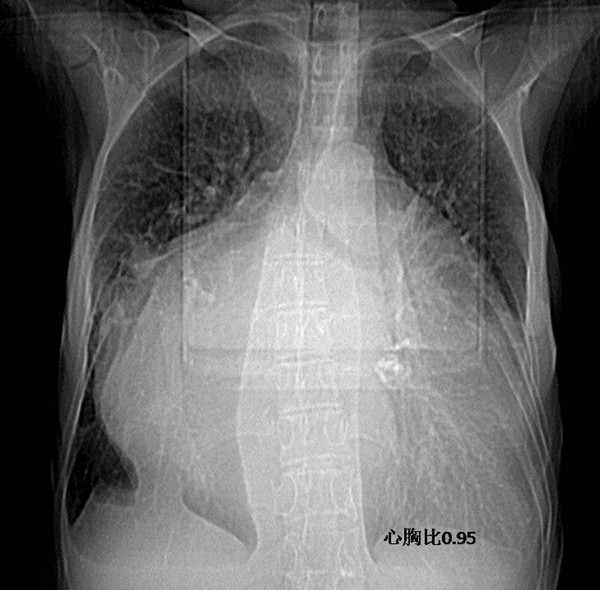

入院后行相关检查,患者的心脏让所有人大吃一惊,胸部CT检查发现心脏极度扩大,心胸比达0.95(注:心胸比正常值约为0.40-0.50,大于0.60即为心影重度增大),极度瘦弱的胸腔基本被心脏填满,这是心外科有史以来接诊的最大心脏!心脏超声提示:风心瓣膜病,二尖瓣狭窄(重度),开口面积仅为0.7cm2(注:正常成人二尖瓣开口面积为4-6cm2),合并关闭不全,返流(极大量);主动脉瓣狭窄(重度)合并关闭不全,返流(少量);三尖瓣返流(极大量);肺动脉高压(重度);左心收缩功能测值明显减低,EF0.41。